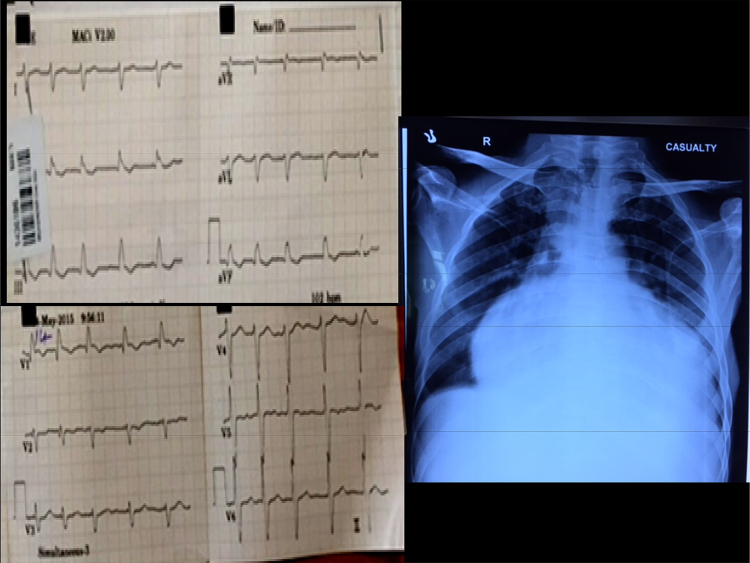

Fig. 1.

The 12-lead ECG in the left panel shows atrial fibrillation, right axis deviation, right bundle branch block and non-specific ST-T changes. Right panel shows chest skiagram in the antero-posterior view. Note globular cardiomegaly with pulmonary oligemia.

A 32-year-old gentleman presented with exertional dyspnea, fatigue, and pre-syncope of three years’ duration. Physical examination revealed a thin-built young man with supine blood pressure 102/82 mmHg, pulse rate 102/min; the rhythm was irregular, and jugular venous pressure was markedly elevated with prominent V waves and neck nodding associated with bilateral jugular vein distension with each heart beat. There was significant non-tender pulsatile hepatomegaly. Precordial examination revealed quiet precordium on palpation, faint heart sounds with wide variably split second sound, and a 2/6 systolic murmur. Hematological parameters and plasma biochemistry were normal. A 12-lead electrocardiogram revealed right axis deviation, atrial fibrillation with an average ventricular rate of 102/min, complete right bundle branch block and non-specific ST-T changes (Fig. 1). A plain chest skiagram showed cardiomegaly (cardiothoracic ratio −70%) and oligemic lung fields (Fig. 1).